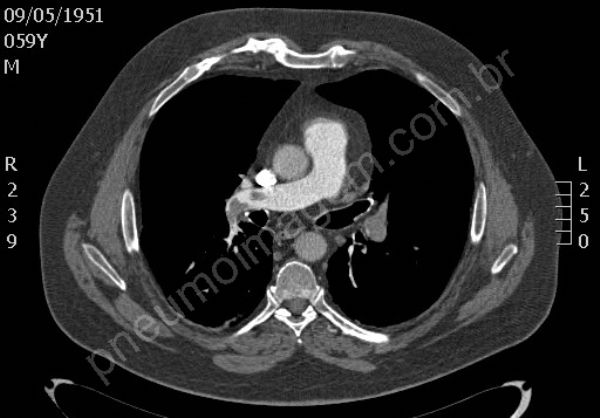

Tromboembolia pulmonar (TEP). Na sequência tomográfica observam-se trombos localizados no tronco da artéria pulmonar e nos principais ramos segmentares à esquerda. Os trombos na bifurcação do tronco pulmonar à direita estendem-se para ramos segmentares do lobo superior, para a interlobar descendente e ramos segmentares do lobo médio. O paciente apresentava também trombose venosa profunda (TVP) na veia femural esquerda, fator de risco importante para TEP. Chaves: tromboembolismo, embolia pulmonar.

Pulmonary thromboembolism (PTE). In tomographic sequence are observed thrombi located in the main pulmonary artery and major segmentary branches left. Thrombi in the bifurcation of the pulmonary trunk right extend to segmentary branches of the upper lobe, extend to descending interlobar and segmentary branches of the middle lobe. The patient also presented deep vein thrombosis (DVT) in the left femoral vein, an important risk factor for PE. Keys: pulmonary embolism (PE).